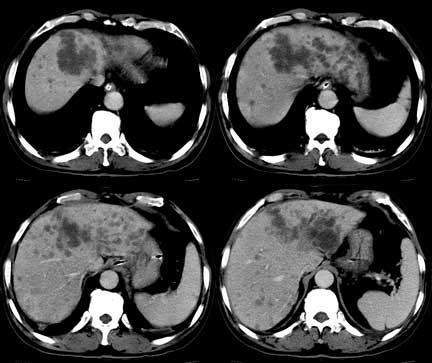

患者 男性 65岁,2005年8月行胆管癌切除术(切除胰头 胆囊及十二指肠),今行ct复查,请会诊,有没有复发?(近期患者发烧,重度黄疸)

是单纯复发还是复发伴肝内转移?我个人认为应当再考虑一下,并倾向于后者。肝总管下端内、后侧见不规则软组织块影,部分侵入肝总管内。其边缘凸凹不平且模糊不清,渐进性不均匀强化。肝总管于此处管径突然变小,其上肝总管显著扩张,内见较均匀液性密度,管壁也很光整。肝内多发低密度病灶用复发引起的肝内胆管扩张显然不能解释的通,病灶分布与胆内胆管的走行不一致。而且随着时间的延续病变更加清晰,没有强化,部分还可见牛眼征。

肯定是:胆管复发并肝内广泛转移,还有肝及胆总管周围网膜炎性改变。腹腔干后第三层面腹膜后血管间结节状影,淋巴结肿大可能,这上面没法看清!

考虑复发并转移,肝门区胆管扩张,左肾多发囊肿可能.腹腔淋巴结转移.